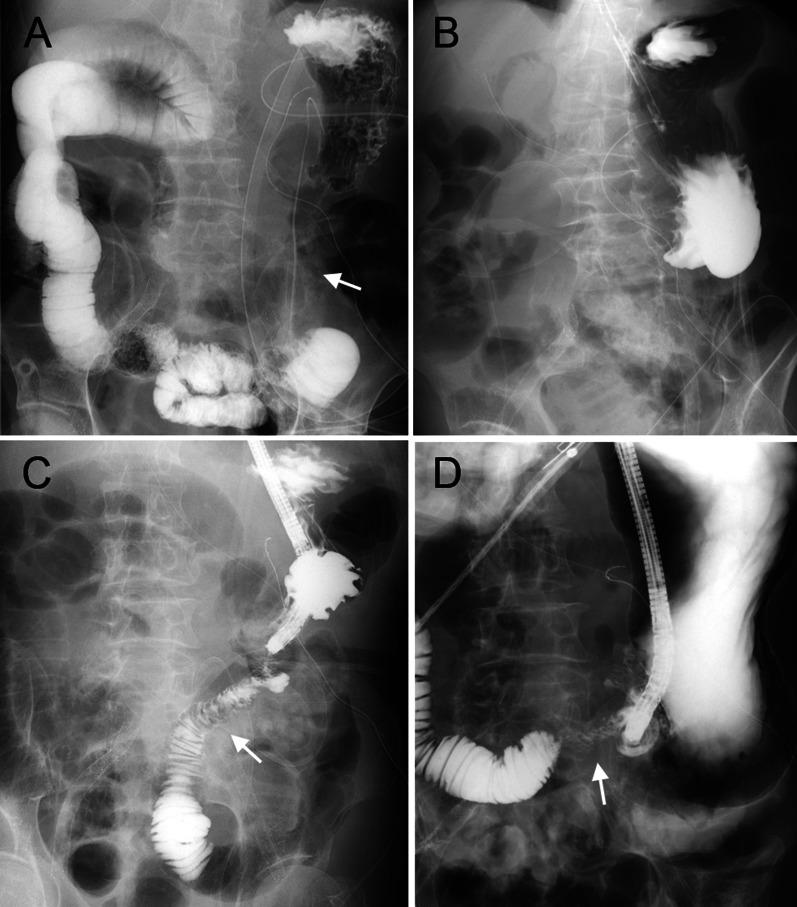

The patient was an 85-year-old man with pancreatic cancer and intestinal malrotation. He underwent pancreaticoduodenectomy with modified Child's reconstruction. Because the ascending colon and efferent loop twisted easily, we fixed the ascending colon to the abdominal wall. Thereafter, right twist and stenosis of the efferent loop occurred. On the 22nd day after the initial surgery, detorsion and Braun anastomosis were performed for efferent loop fixation. Postoperative oral intake was good, and the patient was discharged from our hospital on the 24th day after the reoperation.

This is a rare case of pancreaticoduodenectomy with malrotation following reoperation due to a complication after Child's reconstruction. In similar cases of intestinal malrotation, it is important to consider avoiding coaxial positioning of intestinal parts and an upper abdominal space while selecting a reconstruction method.